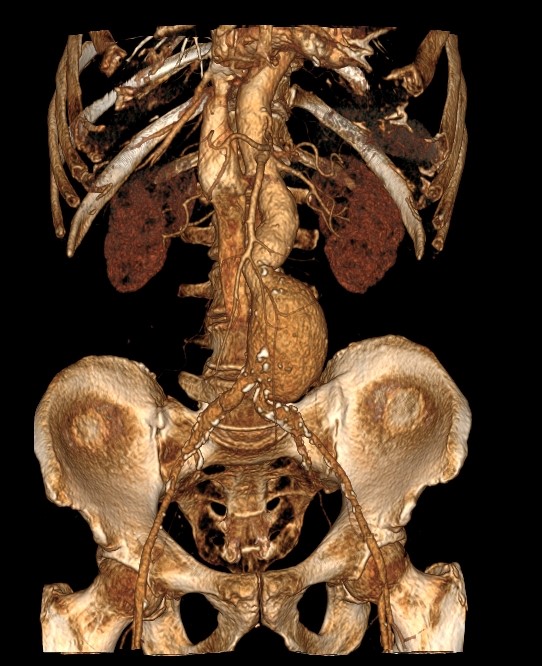

При помощи цифровых приложений данные, полученные при сканировании, трансформируются в трехмерные изображения сосудистой системы. Это позволяет оценить пространственное соотношение анатомических структур и часто применяется в ходе предоперационной подготовки и для оценки успешности проведенной операции.

Аорта – это самый крупный кровеносный сосуд в организме человека. Брюшная аорта является продолжением грудного отдела аорты и расположена ниже аортального отверстия диафрагмы. На уровне 4-5 поясничных позвонков находится бифуркация аорты, где она делится на две общие подвздошные артерии, несущие кровь к нижним конечностям.

От брюшной аорты отходит несколько висцеральных ветвей,  кровоснабжающих внутренние органы. К ним относятся: почечные артерии, чревный ствол, который кровоснабжает органы пищеварения, верхняя и нижняя брыжеечные артерии, питающие кишечник, яичковые артерии у мужчин, яичниковые – у женщин.

В брюшной части аорты нередко возникает истончение и локальное расширение стенки сосуда – так формируется аневризма аорты. Долгое время аневризма может существовать бессимптомно и проявиться только при расслоении стенки (расслаивающая аневризма) или при разрыве аневризмы, что в большинстве случаев заканчивается летальным исходом.